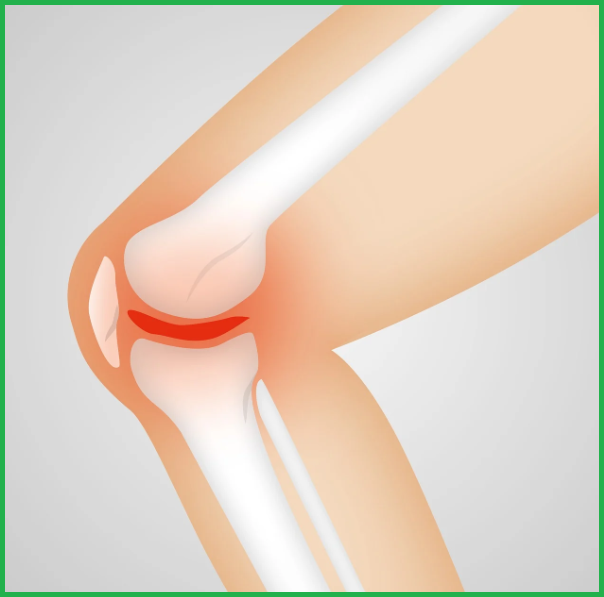

2) 퇴행성 변화(관절염)

노화와 함께 연골이 닳거나 관절에 염증이 생기는 경우, 관절염이 발생합니다. 대표적인 질환으로는 퇴행성 관절염과 류마티스 관절염이 있습니다.

● 전방 십자인대 파열: 스포츠 손상으로 인대가 완전히 끊어진 경우 수술이 필요합니다.

● 퇴행성 관절염 말기: 연골이 완전히 닳아 무릎 관절이 제대로 기능하지 못할 때 인공관절 치환술을 시행합니다.

● 반월상 연골 손상: 심한 손상으로 인해 무릎 움직임이 제한되고 통증이 지속될 때 수술을 고려해야 합니다.